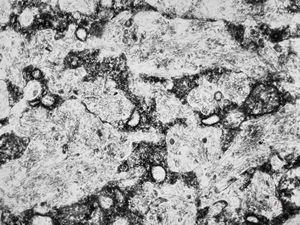

M, 1y. | gangliosidosis - liver